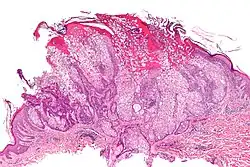

Adenoma sebáceo

Un adenoma sebáceo es un tipo de adenoma que provoca una enfermedad cutánea, y consiste en un tumor benigno de crecimiento lento, habitualmente una pápula o nódulo de color rosa, carne o amarillo.[1][2]